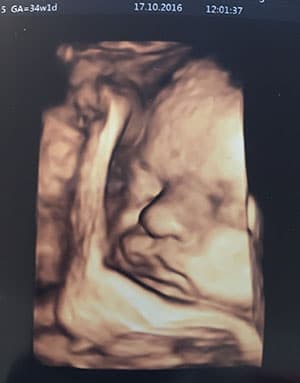

7. Meine 35. SSW (16.10.2016-22.10.2016)

Ich hatte ja ein bisschen Sorge, dass man wegen meines versteiften Rückens von vorne herein zu einem Kaiserschnitt raten würde. Das war zum Glück nicht der Fall und alle meinten, dass das wahrscheinlich kein Problem sein wird, selbst die PDA ist machbar, da meine Wirbelsäule weiter oben steif ist. Über diese Nachricht war ich sehr beruhigt und freue mich nun darauf, dass eine spontane Entbindung zumindest im Rahmen des möglichen liegt :)

Ansonsten geht es mir diese Woche nicht viel anders als die zuvor. Meine Hüfte tut weh, wenn ich mich zuviel bewege (und manchmal auch einfach so) und das Sodbrennen abends ist ohne eine Tablette kaum auszuhalten. Der Bauch wird jetzt langsam wirklich groß und spannt vor allem abends recht unangenehm. Das Öl gegen Schwangerschaftsstreifen hilft dabei dieses Gefühl etwas zu verringern und bis jetzt ist auch noch kein Streifen in Sicht. Allerdings kommen diese ja auch manchmal erst ganz zum Ende.